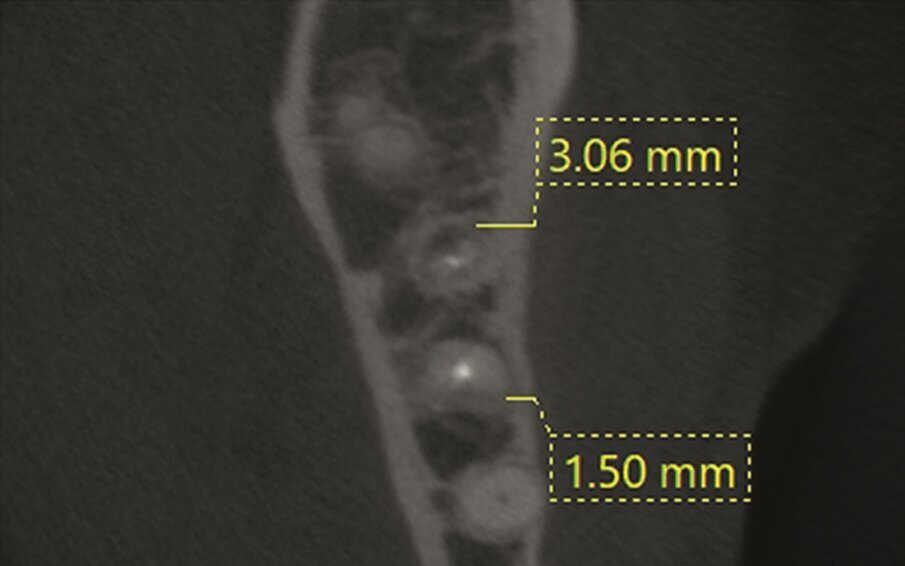

Fig. 1a–d: Pre-op CBCT scan of tooth #36. The axial (a), …

…and sagittal views (c) showed a hypo-dense zone around the apical third of the mesial and distal roots and intact cortical buccal bone.

A template that marked the limits of a cortical window to accurately reach the apical area of both roots was designed (d).

A 63 year old female patient, with a non-contributory medical history, consulted owing to moderate pain associated with her previously treated mandibular left first molar. CBCT revealed that a mesiobuccal canal had being missed during initial treatment, that the mesial and distal roots were affected by an apical lesion, and that the cortical buccal bone was intact.

Retreatment was done in two appointments, and calcium hydroxide was used as the intra-canal dressing after removing the previous filling material and cleaning and shaping three canals. After one week, root canal therapy was completed. Two months later, symptoms persisted and clinical examination revealed pain on vertical percussion; periodontal probing depth and mobility were within normal limits. CBCT revealed no signs of bone healing (Figs. 1a–c). The diagnosis for tooth #36 was previously treated symptomatic periapical periodontitis, and the treatment of choice was guided EMS.

An intra-oral scan (TRIOS, 3Shape) of the mandible, and the resulting STL file was combined with the DICOM files of the CBCT scan to plan a surgical guide using the Blue Sky Bio software. A template that marked the limits of a cortical window to accurately reach the apical area was designed and printed (Fig. 1d).